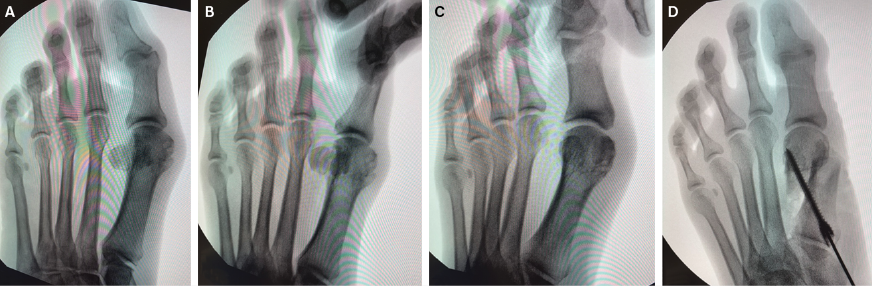

When performing a bunion correction surgery, surgeons often strive for frontal plane correction with physical rotation of the bone.1,2 One technique includes using a Kirschner wire (K-wire) as a joystick to rotate the direction of the osteotomy in the frontal plane out of valgus or eversion. In the senior author’s experience, when performing the minimally invasive technique for HAV, the frontal plane correction is a vitally important step.

Below we describe the senior author’s preferred technique for incorporating the frontal plane into correction for MIS HAV procedures. Following a standard prep of the lower extremity, the surgeon makes a stab incision at the medial aspect of the first metatarsal neck, specifically, at the metaphyseal-diaphyseal junction. Next, one uses a periosteal elevator to create a pathway within the soft tissue envelope medially, superiorly, and inferiorly to create a safe working corridor for the burr. Insertion of the burr takes place perpendicular to the long axis of the metatarsal. This then allows to surgeon to use that burr to create a osteotomy through the metatarsal neck. The surgeon then proceeds to complete the minimally invasive osteotomy by creating their desired type of osteotomy.

Once the osteotomy is complete, one can use a curved hemostat or industry device to stabilize and to adduct the proximal portion of the metatarsal at the osteotomy site, with a goal of adducting the first metatarsal shaft. The surgeon can distract, shift, and/or rotate several structures out of valgus, including the head of the first metatarsal, the sesamoid complex, and the great toe. In this one motion, one can also translate these structures in the transverse plane into a more neutral anatomic alignment. The head of the metatarsal is pushed laterally and possibly into slight adduction in order to correct the transverse plane deformity.

When manipulating the hallux in the frontal plane, the surgeon can manually grasp and rotate the hallux and/or the distal first metatarsal (distal phalanx, proximal phalanx, distal metatarsal head and 2 seasmoids) as one unit/complex. By not performing a lateral release or performing any kind of dissection about the first metatarsophalangeal joint, one keeps the natural anatomy presented in valgus in malalignment intact, allows the entire complex (distal and proximal phalanges, sesamoids, and metatarsal head) to function as one unit, and avoids destabilizing the soft tissue attachments. Fluoroscopy can help one to observe the desired frontal plane rotation. Once obtaining the desired reduction in all planes, a K-wire can provide temporary fixation. Next, a screw may be inserted from proximal-medial to distal-lateral for permanent fixation.